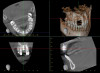

(21.) Postoperative periapical radiograph taken immediately after placement of the implant at site No. 8 demonstrating implant positioning centered with the planned location of the gingival zenith and two titanium alloy tacks that were used to stabilize the resorbable membrane apically.

Figure 21

(22.) Immediate postoperative CBCT scan.

Figure 22